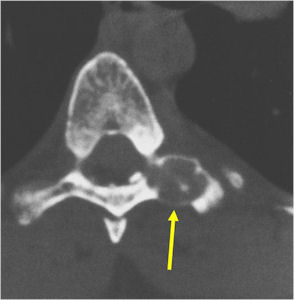

Radiographic imaging is used to help form a diagnosis. These include X-Ray, MRI, CT and Bone Scans

An example of an CT is shown.